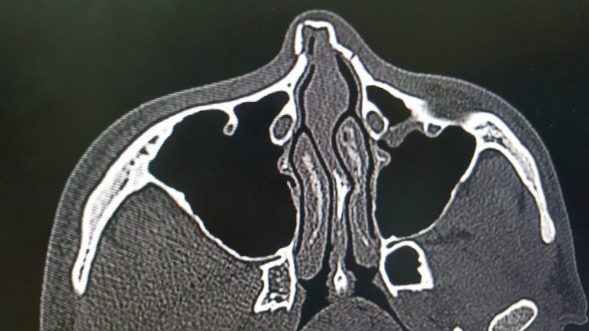

ภาพเอ็กซเรย์จมูกของ คิม จอง-มิน

ซึ่งล่าสุดทีมแพทย์ระบุว่า คิม จอง-มิน กระดูกบริเวณดั้งหักทั้งซีกซ้ายและขวาจากการโดนกระแทก และวันพุธนี้ คิม จอง-มิน จะต้องบินไปกลับไปยังประเทศเกาหลีใต้ เพื่อผ่าตัดโดยด่วนและคาดว่าจะต้องพักเป็นอาทิตย์ และอาจจะชวดลงสนามในเกมเปิดบ้านรับทีม ราชบุรี มิตรผล เอฟซี ในวันที่ 28 มีนาคมนี้